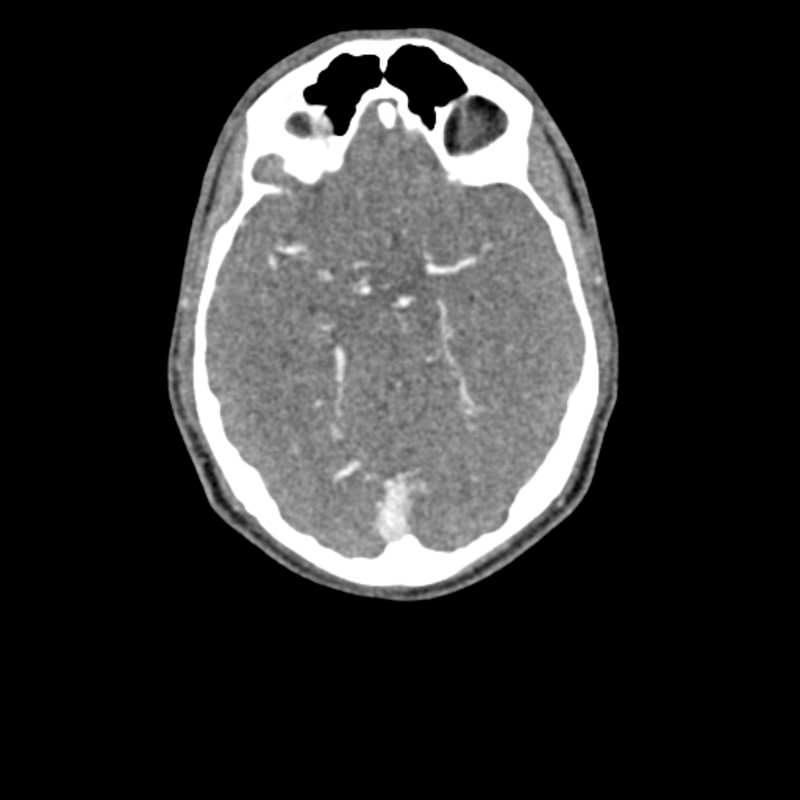

Dieses Phantom ist aus echten Patientendaten erstellt und wird mit neuester Technologie hergestellt. Knochen, Gefäße und Weichteilgewebe werden authentisch dargestellt mit realistischen CT-Werten für alle Gewebe bei 120 kVp Röhrenspannung in der CT. Wenn das Phantom vorwiegend bei anderen Röhrenspannungen (z. B. 100 kVp) eingesetzt werden soll, kann die Kalibrierung der CTWerte auf Wunsch entsprechend angepasst werden. Das Phantom liefert realistische Gewebekontraste in der Röntgen-Bildgebung. Lufträume sind durch ein Material mit etwa -80 Hounsfieldeinheiten aufgefüllt.

Das Kopf - Phantom liefert eine äußerst realistische Simulation einer Kopf- und Hals-CT-Angiographie (mit arterieller Kontrastierung) eines Patienten mit einer arteriovenösen Malformation auf der rechten Seite. Das Phantom wird in originalgetreuem Maßstab geliefert und beinhaltet die Halswirbelsäule bis zur Grundplatte des fünften Halswirbels.